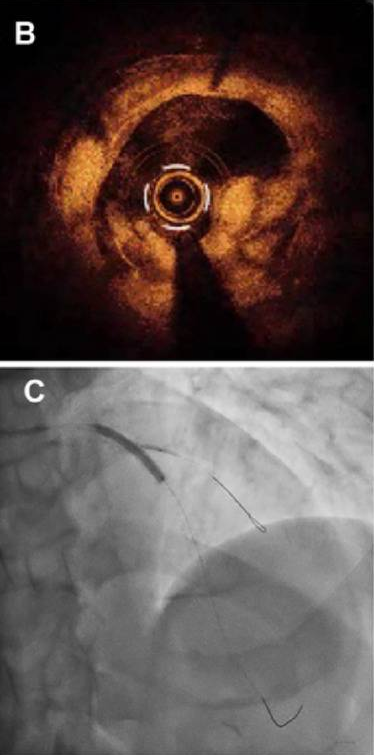

为了处理突入管腔的组织,首先使用了准分子激光冠状动脉成形术(ELCA; Philips, USA; 1.4 mm C-type catheter, 60 mJ/mm², 40 Hz)治疗该病变。消饰后血管造影未显示明显的血流限制性并发症(视频2)。消饰后OCT显示突出组织部分缩小(图B)。定量OCT分析显示,突出组织的面积从准分子激光治疗前的4.49mm2降至治疗后的3.82mm²,提示突出的新生内膜组织得到有效减容。

B 准分子激光治疗后的OCT图像显示突出斑块部分缩小;

C DCB扩张联合对吻球囊扩张后的最终血管造影结果;

激光治疗后,采用3.5×13mm刻痕球囊(Aperta NSE)进行病变预处理。刻痕球囊扩张后,对角支出现血流减慢,采用1.5×10mm半顺应性球囊(Ryurei)扩张处理,对角支血流恢复。